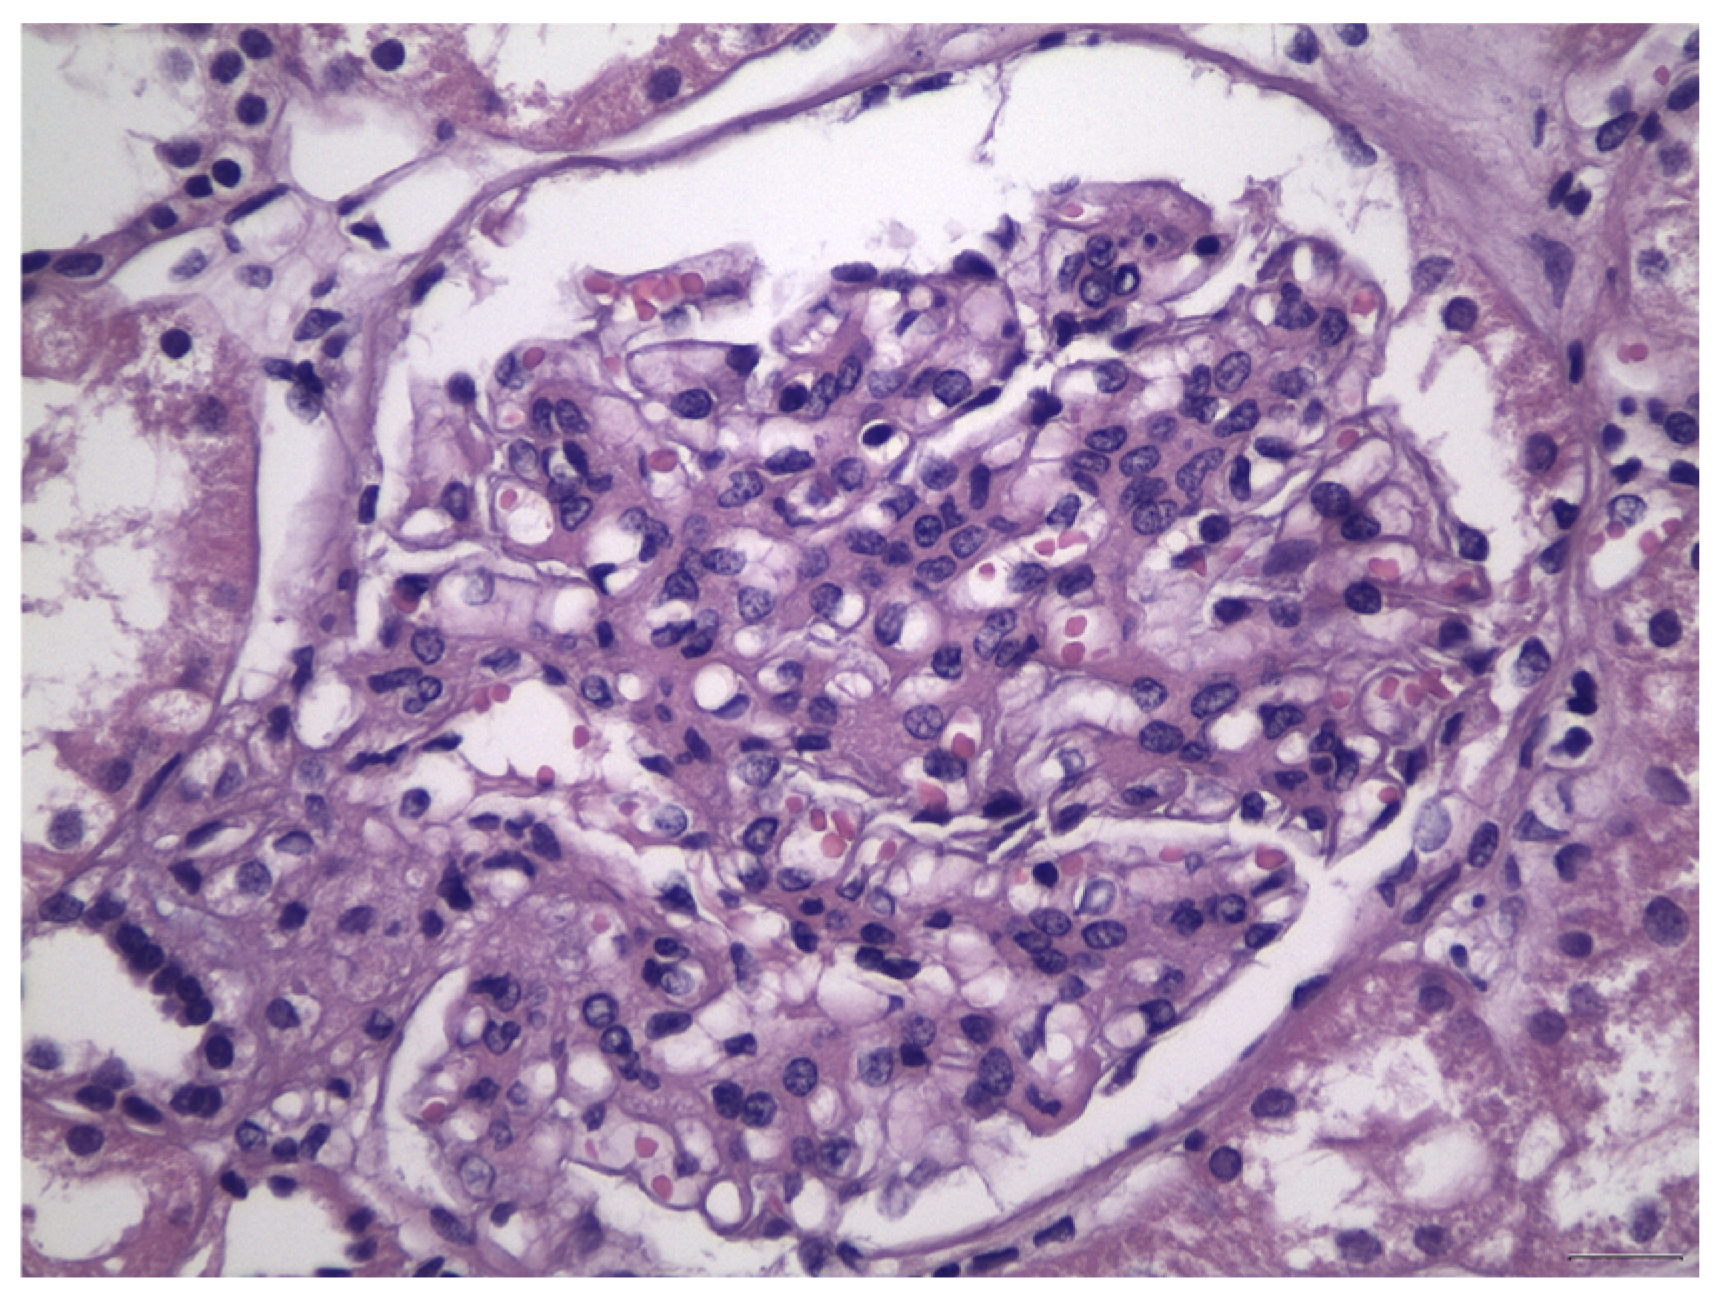

- Berger, J.; Hinglais, N. Intercapillary deposits of IgA-IgG. J. D’urologie Nephrol. 1968, 74, 694–695. [Google Scholar]

- Haas, M. Histologic subclassification of IgA nephropathy: A clinicopathologic study of 244 cases. Am. J. Kidney Dis. 1997, 29, 829–842. [Google Scholar] [CrossRef]

- Cattran, D.C.; Coppo, R.; Cook, H.T.; Feehally, J.; Roberts, I.S.D.; Troyanov, S.; Alpers, C.E.; Amore, A.; Barratt, J.; Berthoux, F.; et al. The Oxford classification of IgA nephropathy: Rationale, clinicopathological correlations, and classification. Kidney Int. 2009, 76, 534–545. [Google Scholar] [CrossRef] [PubMed]

- Roberts, I.S.D.; Cook, H.T.; Troyanov, S.; Alpers, C.E.; Amore, A.; Barratt, J.; Berthoux, F.; Bonsib, S.; Bruijn, J.A.; Cattran, D.C.; et al. The Oxford classification of IgA nephropathy: Pathology definitions, correlations, and reproducibility. Kidney Int. 2009, 76, 546–556. [Google Scholar] [CrossRef] [PubMed]

- Jennette, J.C.; Olson, J.L.; Silva, F.G.; D’Agati, V.D. Heptinstall’ s Pathology of the Kidney, 7th ed.; LWW: Philadelphia, PA, USA, 2015. [Google Scholar]